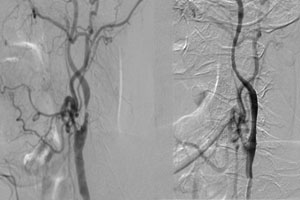

Trường hợp 1:

Bệnh nhân nam, 71 tuổi, hẹp động mạch cảnh trong trái, chóng mặt say sẩm, yếu 1/2 phải.

1a: trước đặt stent.                            Hình 1b: sau đặt stent

Sau can thiệp nong và đặt stent, các triệu chứng bệnh nhân cải thiện, bớt chóng mặt, tay chân phải mạnh hơn, đi lại bình thường.